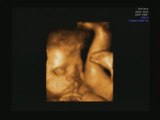

Echographie 3D

L'echographie 3D de notre fille